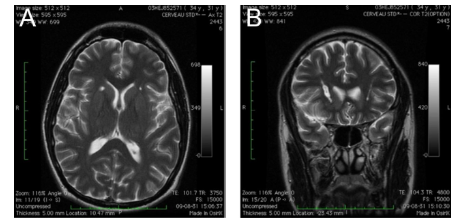

Surgical Lesioning

In the case of severe treatment-refractory OCD, an OCD patient might be a candidate for neurosurgical treatment. Procedures were undertaken to disconnect brain targets in the emotional system physically. The most common lesioning treatments for treatment-refractory OCD are anterior capsulotomy and anterior cingulotomy, performed using traditional surgical techniques or stereotactic radiosurgery. Overall, lesioning procedures offer therapeutic benefits to 30–60% of patients with treatment-refractory OCD.

Figure 4. Anterior Capsulotomy (jnnp.bmj.com)